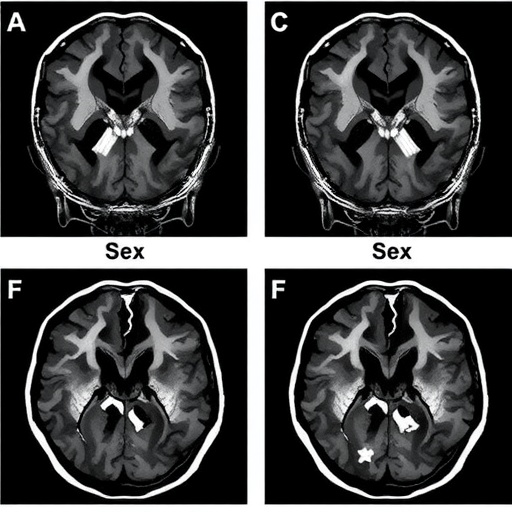

The c-rel gene plays a pivotal role in regulating neuroinflammatory responses, a critical component of many neurodegenerative diseases including Parkinson’s. In the absence of this gene, as demonstrated in the c-rel knockout model, there are observable differences in how the nigro-striatal pathway—the region often affected in Parkinson’s disease—degenerates. The study highlights that while both male and female mice exhibited dopaminergic neuron loss, the rate and extent of degeneration differed between the sexes, revealing potential targets for therapeutic intervention.

Furthermore, the researchers conducted a comprehensive analysis of the behavioral aspects associated with Parkinson’s disease in these models. Male c-rel knockout mice displayed pronounced motor deficits compared to their female counterparts. This variation in behavioral phenotype suggests that neuroprotective or neurodegenerative factors could be sex-specific, necessitating a more nuanced approach when devising treatments or supportive interventions aimed at improving quality of life for Parkinson’s patients.

Moreover, the research team delved into the biochemical indices associated with neuroinflammation in their model. Increased levels of inflammatory markers were consistently observed in male mice, aligning with the increased degeneration of nigro-striatal neurons. These findings advocate for further investigation into the role of inflammation as a mediator of neurodegeneration, shedding light on potential anti-inflammatory treatments that could serve as adjuvants to traditional therapeutic approaches.